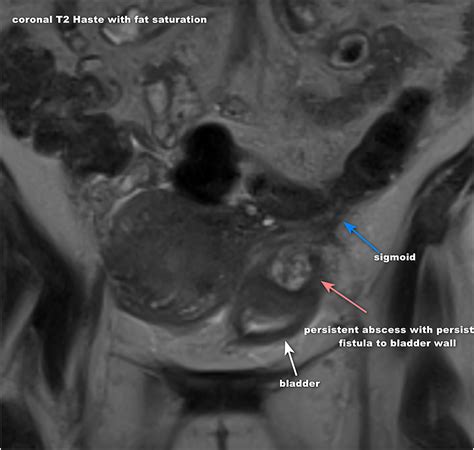

Diagnosing a colovesical fistula involves a combination of clinical evaluation, imaging studies, and sometimes endoscopic procedures. The diagnostic process typically includes:

• Imaging studies: CT scans, MRI, or barium enema can help visualize the fistula.